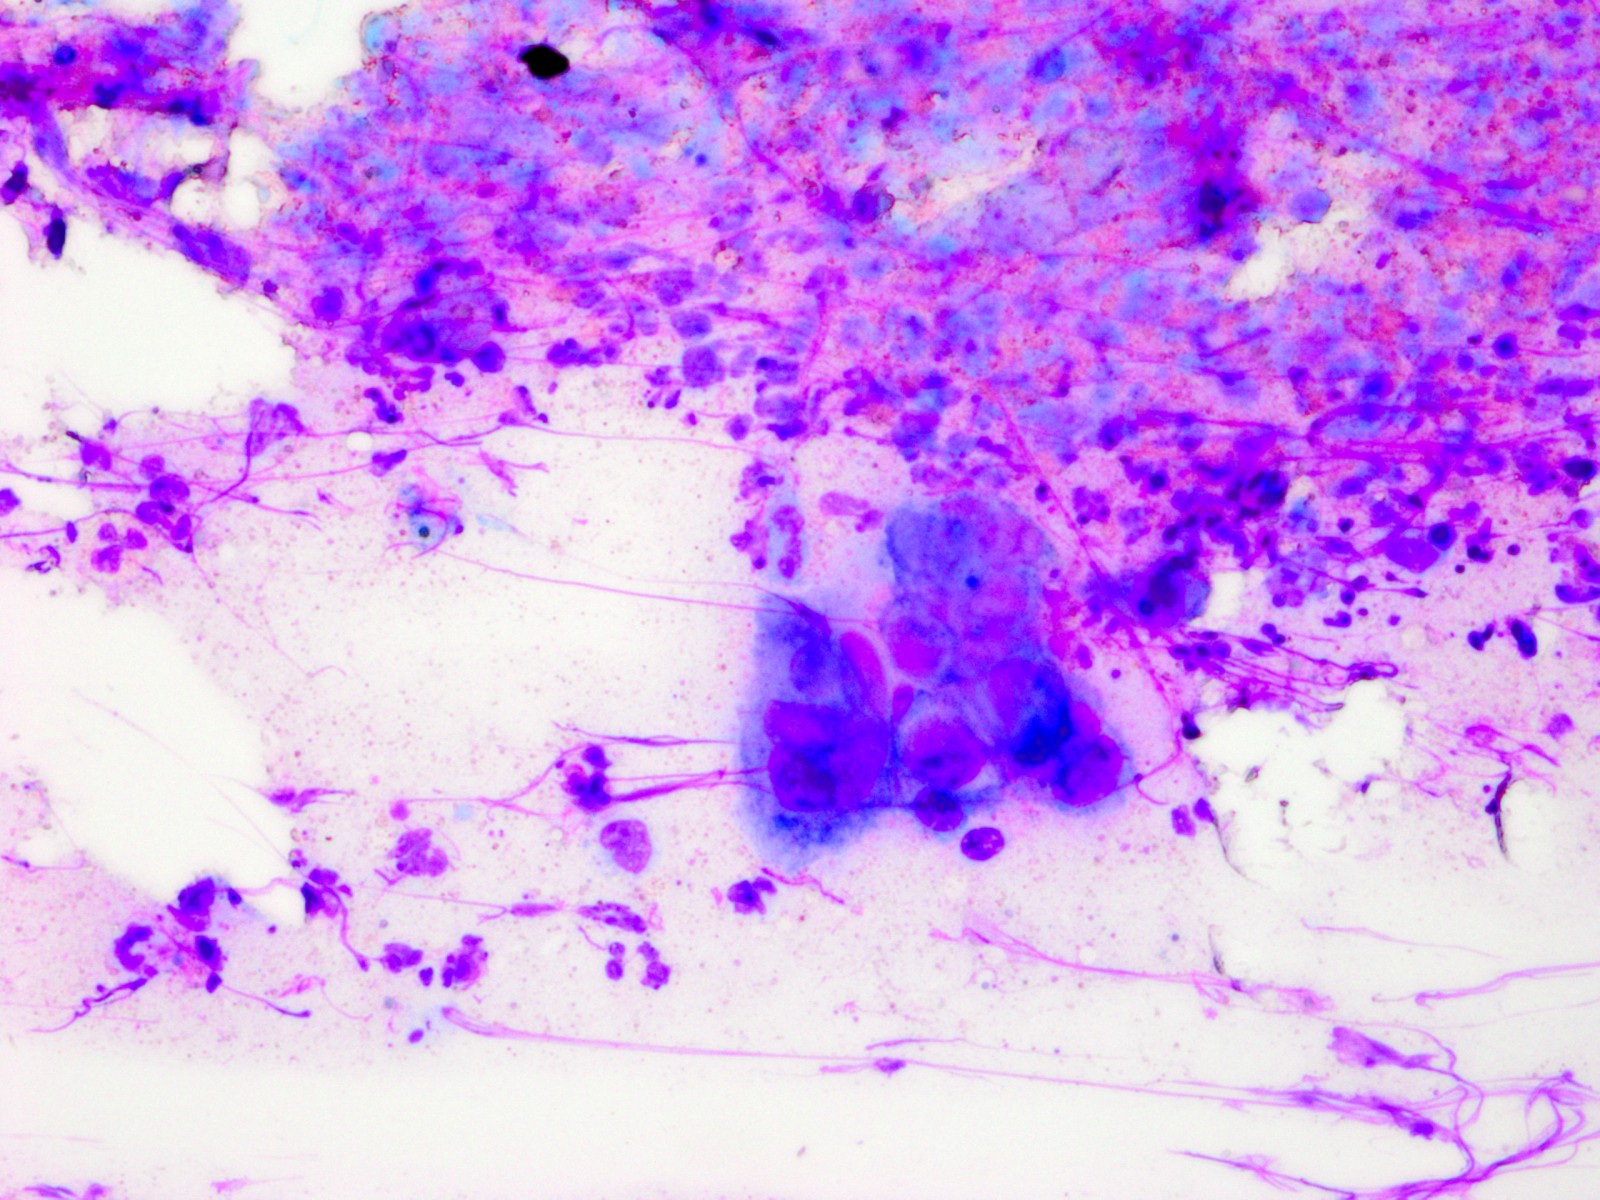

De Tzanck reuscellen hebben in het Diff-Quick preparaat een lichtblauw (basofiel)

cytoplasma en een homogene donkerblauwe of paarse kern (hyperchromatisch, sterk

aankleurend), en zijn zeer groot, veel groter dan een granulocyt. Het zijn geen

macrofagen of Langhanse reuscellen, het zijn conglomeraten van grote epitheliale

cellen (keratinocyten). Er kunnen in het preparaat ook losse van deze grote

hyperchromatische epitheelcellen liggen, maar diagnostisch is het vinden van

een klompje waarbij het cytoplasma samengesmolten is en de kernen tegen elkaar

aanliggen. Losliggende grote afgeronde epitheelcellen (Tzanck cells) kunnen